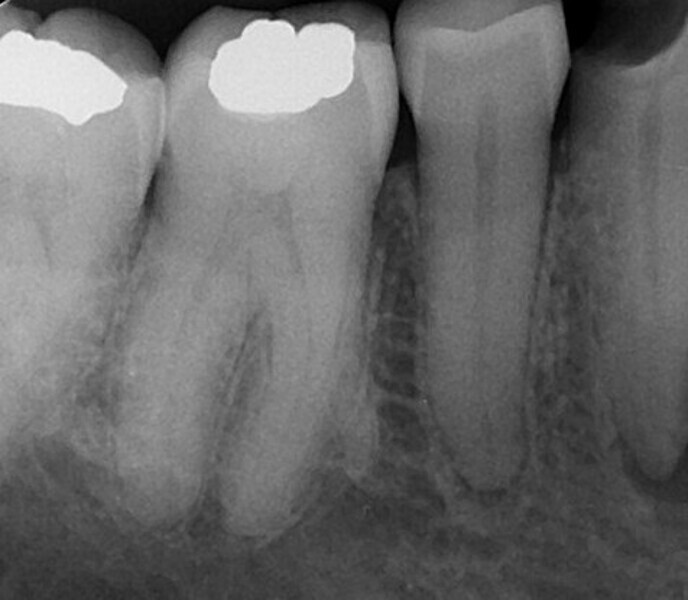

Shaping a Type V mandibular premolar with VDW.ROTATE